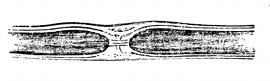

Fig. 2—A cross section of

the skin. (Gray)